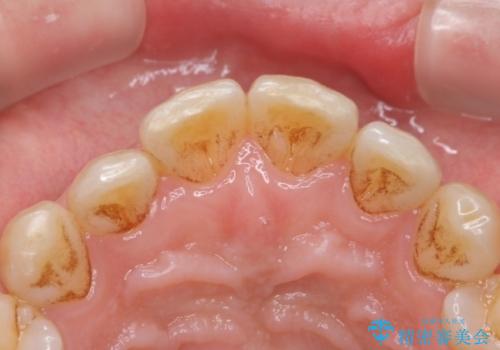

PMTCによる着色除去

- 着色が気になるとのことで来院された。

着色だけでなく、歯石やバイオフィルムの除去、ハイドロキシアパタイト配合のトリートメントで仕上げ磨きまで行います。